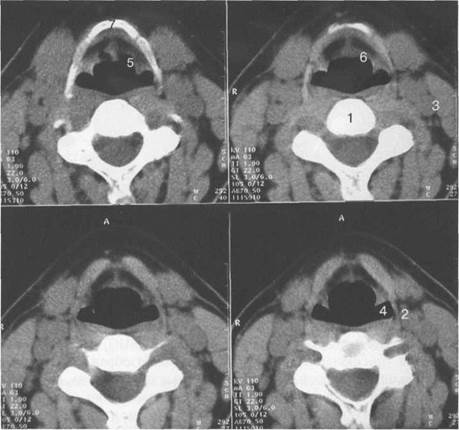

На срезе, выполненном на уровне подъязычной кости (рис. 6.3), визуализируется вход в гортань, ограниченный по бокам просветами грушевидных синусов. Латеральнее тела позвонка с двух сторон располагаются внутренняя яремная вена и общая сонная артерия. Кпереди от воздушного столба гортани определяются надгортанник, преднадгортанниковое пространство, тело подъязычной кости. Преднадгортанниковое пространство выполнено жировой клетчаткой и имеет денситометрическую плотность от —20 до —70 HU. Денситометрическая плотность надгортанника выше, варьирует в широком диапазоне: от —6 до 120 HU.

Рис. 6.3. Компьютерные томограммы гортани

1 — тело позвонка; 2 — внутренняя яремная вена;

3 — общая сонная артерия;

4 — грушевидный синус;

5 — черпалонадгортанная складка; 6 — надгортанник; 7 — подъязычная кость.